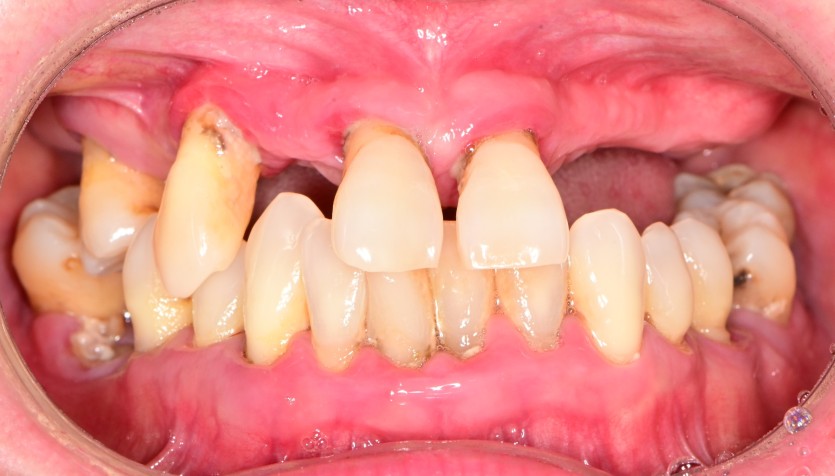

전체 임플란트 증례입니다.

18개의 임플란트로 완성하였습니다.